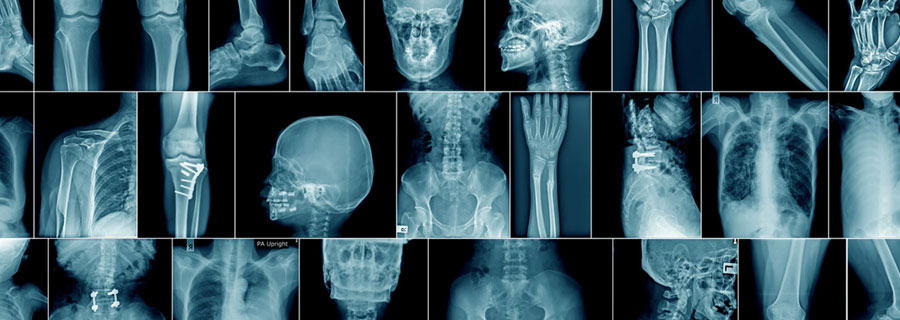

The Precision Diagnostic Centre, located in the vibrant city of Sanpada in Navi Mumbai, is a state-of-the-art healthcare facility committed to providing accurate and reliable diagnostic services.